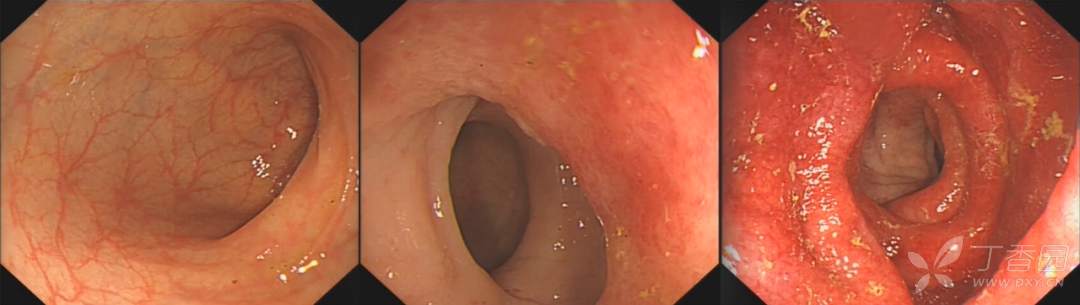

专科查体:蹲位排便后可见肛门直肠全层脱出,呈同心圆状,长约 5 cm,指检肛门稍松弛,距肛缘 6 cm 未及明显肿物,指套退出无染血,镜检粘膜松弛。

盆腔 MRI:直肠全层脱垂。肠镜:直肠粘膜松弛,直肠粘膜炎症。